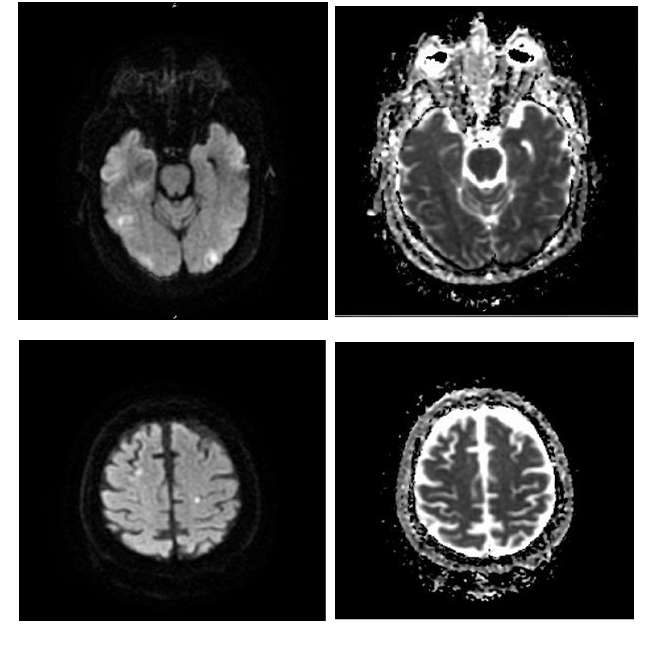

Pulmonary embolism was strongly suspected, therefore a heparin infusion was initiated and a contrast enhanced chest CT scan was performed. This demonstrated bilateral pulmonary infiltrates and effusion but did not reveal any findings of pulmonary embolus. Doppler ultrasound of the lower extremities did not show evidence of thrombosis. Heparin was then discontinued. The platelet count which was initially normal, decrease dove several days to anadir of 96,000 per micro liter but then normalized. Serotonin release assay and platelet factor 4 antibody assay were negative. Urine stained with Oil Red O was negative for findings of fat globules. Initial head CT did not reveal any acute hemorrhages or signs of chronic infarcts. However, a repeat CT scan four days after admission revealed hypodensity in the posterior right temporal lobe consistent with an infarct. A subsequent MRI of the brain showed multiple acute infarcts in bilateral water shed areas, thought to be most likely due to athero­thromboemboli (Figure 3). Supportive management included intravenous fluids, enteral nutrition, vasopressors and mechanical ventilation. A diagnosis off at emboli syndrome was established after careful consideration of results from multiple laboratory and imaging studies along with the patient’s initial presentation and clinical course. With supportive care, she was weaned off vasopressors after 2weeks in the intensive care unit. A follow up echocardiogram per formed after seven days showed normalization of right ventricular size and function. She demonstrated digress of residual confusion when she was transferred to a subacute rehabilitation facility after twenty ­three day so hospitalization. A subsequent admission several weeks later was reported after patient was still confused disoriented and perceived to be depressed and dehydrated. Condition improved after medical management but with preserved minimal residual cognitive deficit. She has not required any orthopedic procedures for the pelvic ramus fracture.

Figure 3 MRI of the brain showing atherothrombotic emboli in bilateral watershed areas. Diffusion weighted image at level 13 (top left) with corresponding non­diffusion weighted image (top right); level 25 (bottom left) with corresponding non­diffusion image (bottom right).